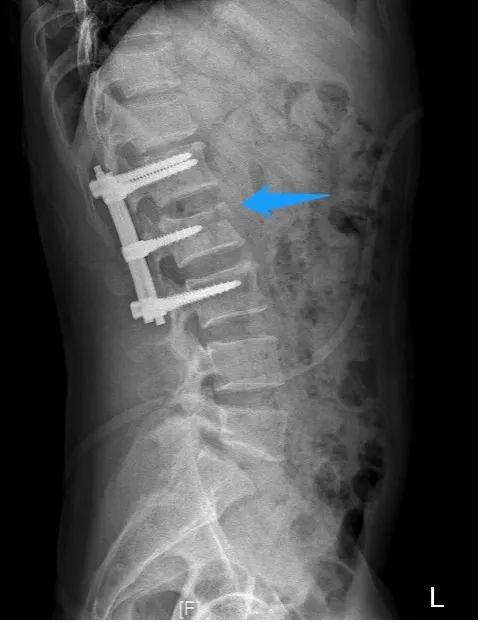

腰椎术前X线侧位片

潘磊副院长表示,只有尽快手术患者才有站起来的希望。经患者及其家属知情同意,手术由潘磊副院长指导,薛厚军副主任医师主刀,在麻醉科协助下历时2小时成功完成。潘磊副院长说,“骨折完全复位,术中也对神经进行了探查松解,手术非常成功”。